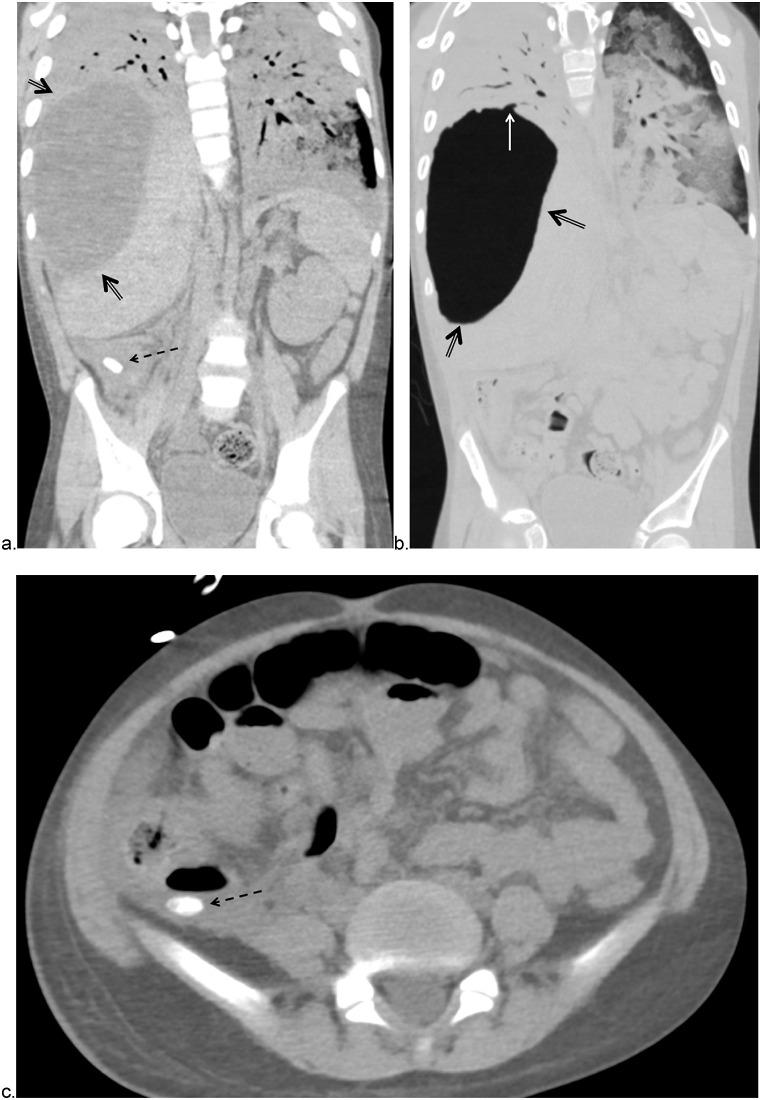

Hypoxic respiratory failure in acute appendicitis: A bronchoperitoneal fistula as the presenting symptom of appendicitis in the setting of pediatric COVID-19.

Symptomatic COVID-19 less frequently affects the pediatric population and is often associated with atypical presenting symptoms. Here we describe a nine-year-old patient who presented with acute hypoxic respiratory failure and was found to have perforated appendicitis, intra-abdominal abscess, and bronchoperitoneal fistula. The rapid progression of this pathology, complex critical care decision making, and ultimate surgical management has not been previously described. Documenting this patient's clinical course and effective treatments may serve to inform and guide the medical community and pediatric care providers as the world continues to combat the COVID-19 pandemic.

有症状的新冠病毒病(COVID-19)较少影响儿童群体,且常伴有非典型的症状表现。在此,我们描述一名9岁患者,该患者出现急性低氧性呼吸衰竭,经检查发现患有阑尾穿孔、腹腔脓肿和支气管腹膜瘘。此前尚未有关于这种病情快速进展、复杂的重症监护决策以及最终手术治疗的描述。记录该患者的临床病程及有效治疗方法,可能有助于在全球继续抗击COVID-19大流行之际,为医学界和儿科护理人员提供信息并给予指导。